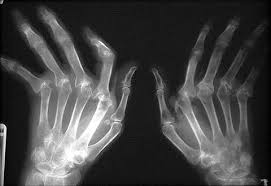

The first step in the diagnosis of arthritis is a meeting between the doctor and the patient. The doctor will review the history of symptoms, examine the joints for inflammation and deformity, as well as ask questions about or examine other parts of the body for inflammation or signs of diseases that can affect other body areas. Furthermore, certain blood, urine, joint fluid, and/or X-ray tests might be ordered. The diagnosis will be based on the pattern of symptoms, the distribution of the inflamed joints, and any blood and X-ray findings. Several visits may be necessary before the doctor can be certain of the diagnosis. A doctor with special training in arthritis and related diseases is called a rheumatologist (see below).